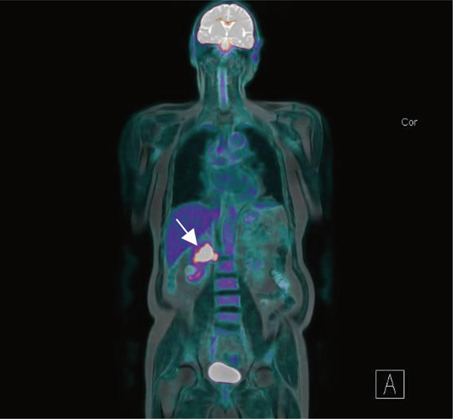

Macroscopic features showed a 45 mm cream-coloured tumour in the mid- to upper pole with no haemorrhage or necrosis (Figure 2). The tumour showed invasion through the IVC wall, extending into the psoas muscle. Histopathology demonstrated a moderately differentiated SCC with associated fibrosis (Figure 3). The tumour also showed extensive lymphovascular invasion and peri-neural invasion involving the vascular margin. Two of the five resected hilar lymph nodes demonstrated involvement, whereas the one resected pre-aortic lymph node did not demonstrate involvement. The patient was referred to a radiation oncologist to discuss the possibility of adjuvant radiotherapy.

Fig 2

Figure 2. Pathological specimen of right kidney post-nephrectomy demonstrating a dense hilar mass.